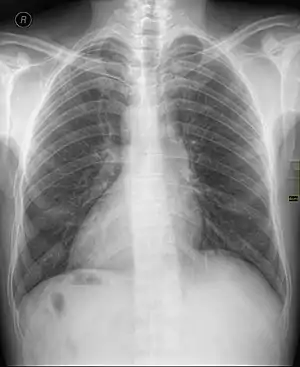

| Chest X ray of a person with dextrocardia situs inversus showing the cardiac apex pointing towards right | |

Dextrocardia (from Latin dextro, meaning "right hand side," and Greek kardia, meaning "heart") is a rare congenital condition in which the apex of the heart is located on the right side of the body, rather than the more typical placement towards the left.[1] There are two main types of dextrocardia: dextrocardia of embryonic arrest (also known as isolated dextrocardia) and dextrocardia situs inversus. Dextrocardia situs inversus is further divided.

Dextrocardia situs inversus refers to the heart being a mirror image situated on the right side. For all visceral organs to be mirrored, the correct term is dextrocardia situs inversus totalis.[4][5]